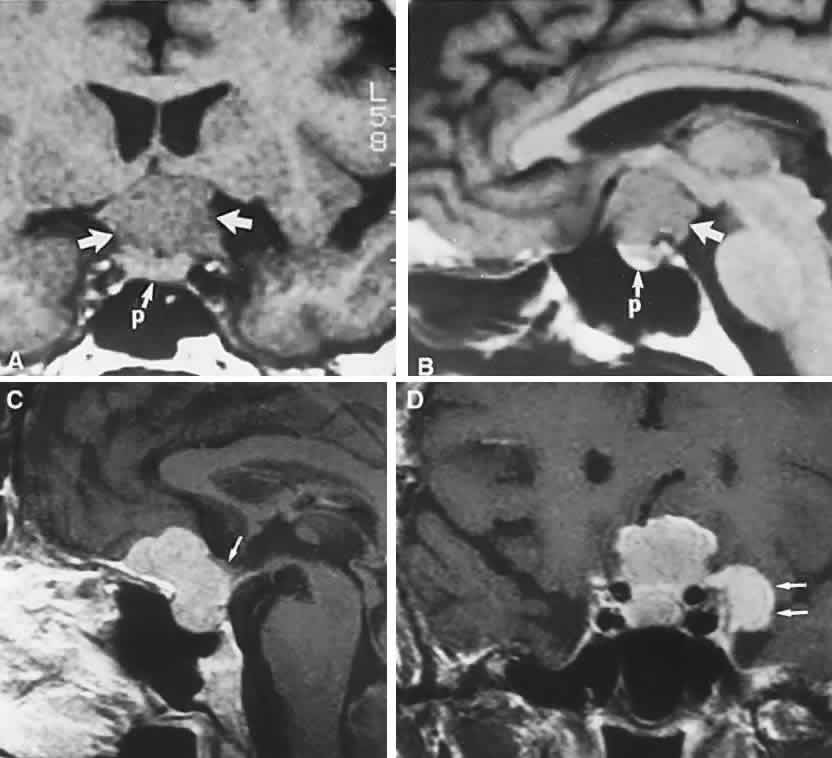

The absence of field defects, for example, in patients undergoing evaluation for amenorrhea, galactorrhea, or sellar enlargement incidentally discovered, does not imply the absence of an adenoma. Obviously, patients with microadenomas, that is, confined within the sella, do not have field defects. From a study24 of 50 cases of pituitary adenomas with chiasmal syndrome, it was concluded that visual disturbance occurs when the chiasm is displaced approximately 10 mm upward (see also Volume 2, Chapter 4, Fig. 6). The modern management of pituitary adenomas should involve several disciplines: current neuroradiologic studies detect microadenomas and provide precise delineation of gross morphology and status of neighboring structures, and mixed MRI signals suggest new or old hemorrhage, cysts, and so forth (Fig. 2); radioimmunoassay techniques assay PRL and other endocrine levels; oral neuropharmacologic agents, such as bromergocryptine, provide a “medical adenomectomy” for hyperprolactinemia and acromegaly; transsphenoidal surgery, including high-illumination microscopical procedures, televised radiofluoroscopic monitoring, and infection control, has all but replaced transcranial approaches; immunohistochemistry techniques have replaced the anachronistic tinctorial designations (e.g., chromophobe, basophilic) with a functional classification.

Fig. 2. Large prolactinoma. Original vision in the right eye (RE) was 8/200, left eye (LE) 1/200, with serum prolactin of 26,000 ng/ml and galactorrhea. Four months of bromocriptine reduced prolactin to 661 ng/ml, vision improved to RE 20/40, LE 20/50. At 3 years, vision was as follows: RE 20/30, LE 20/20; prolactin was 25.9 ng/ml. Enhanced magnetic resonance imaging. Sagittal (A) and coronal (C) images at diagnosis. Sagittal (B) and coronal (D) images at 2-year follow-up, showing dramatic shrinkage of the mass.

In previous decades, chiasmal interference with optic atrophy, but “normal” plain skull films, was referred to as “Cushing's syndrome of the chiasm,” caused by meningiomas, aneurysms, or other noncalcified suprasellar lesions. The modern neuroimaging techniques of enhanced CT, “bone-window” protocols, and gadolinium-contrasted MRI are now exceedingly sensitive in disclosing meningiomas or other parachiasmal masses (Fig. 4). At present, contrast-enhanced CT or MRI precisely demonstrate extra-axial tumor configuration; CT is superior in disclosing calcification or bone changes, but it is inferior for assessing suprasellar or intrasellar extension, postsurgical changes, and vascular displacement or encasement.76 Whether MRI or even MR angiography obviates standard selective arteriography, especially when surgical intervention is contemplated, is moot.

Fig. 4. Magnetic resonance imaging of a suprasellar meningioma (TR, 600 milliseconds; TE, 20 milliseconds). A. Coronal section of a large meningioma (large arrows), isodense to brain. B. Sagittal section. Note the normal sella and pituitary gland (p). Sagittal (C) and coronal (D) sections of a planum meningioma, extending into the sella. Note the upward deflection of the chiasm (arrow in C) and extension to the cavernous sinus (arrows in D).